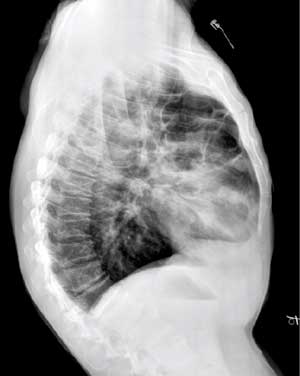

以下是引用向医生在2004-6-30 20:21:28的发言:[br]右上肺有多个薄壁囊状透亮区,其内无明显液平面.[br]意见:右上肺多发性肺囊肿.